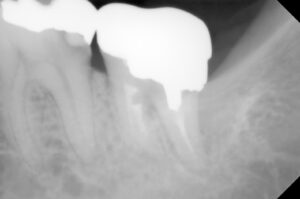

保険にて根の処置をしてレントゲン確認した時に

2017年8月 再来時に左下第二大臼歯のレントゲン

を撮り処置途中歯の被せ物の相談をするもそのままに

2019年7月になってやっとご本人が処置の決断をされ

根の処置が上手くいかないことを説明し、保険で

土台と冠を被せることで納得していただきました。

レントゲンでは神経の詰め物の状態の違い→